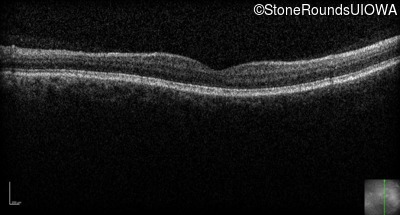

Optical Coherence Tomography - Left - 20/200

Exemplar / OCT Stack

OCT Stack